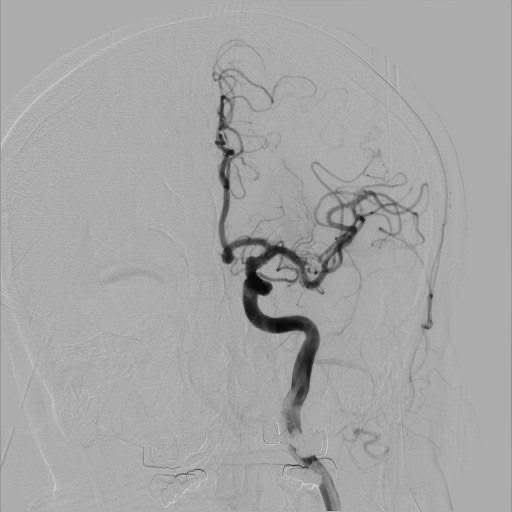

Далі під час КТ ангіографії в лівій середній мозковій артерії виявили тромб. Серцево-судинний хірург, завідувач відділення інтервенційної кардіології, радіології та кардіохірургії Олег Совтус провів пацієнту тромбектомію (оперативне втручання, при якому відбувається механічне видалення тромбу з судини головного мозку).